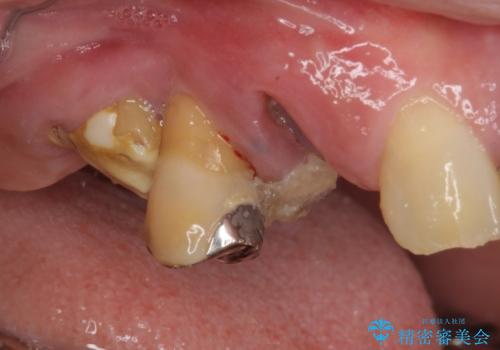

- 歯が破折しているため、抜歯が必要であると近医で診断されてからも放置を続けてしまったとのことで来院された患者様です。

臼歯はもはや咬み合わせに寄与していない状態であり、3歯を抜去してインプラント2本埋入によるブリッジ補綴を計画しました。

セオリーとしては、インプラント補綴治療により奥歯の咬み合わせを確立してから、前歯部の処置を行うことになりますが、初めてのインプラント治療であることや、前歯部の見た目が気になっていることから、前歯の抜歯即時埋入インプラントによる補綴治療を先行して行い、並行して奥歯のインプラント治療を進めて行くこととしました。

抜歯即時埋入インプラントによる補綴治療の特徴は、短期間であることや処置数が少ないことが挙げられます。また、表側の歯肉の陥凹を避けることができるというメリットがあります。しかしながら、今回は歯根破折の程度が酷く、やや膨らみを失うこととなりましたが、スムーズに治療を終えることができました。